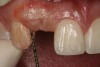

Figure 21   Gingival zenith planning: The location of the gingival zenith for this missing lateral incisor is not fully evident during initial clinical evaluation (Fig 21). Subsequent diagnostic waxing reveals the position of the planned gingival zenith (Fig 22). A thermoplastic template captures the position of the zenith and enables transferring this location to the clinical environment (Fig 23 and Fig 24). Final crown contours are defined by soft-tissue form (Fig 25).

Figure 21

Figure 22  Gingival zenith planning: The location of the gingival zenith for this missing lateral incisor is not fully evident during initial clinical evaluation (Fig 21). Subsequent diagnostic waxing reveals the position of the planned gingival zenith (Fig 22). A thermoplastic template captures the position of the zenith and enables transferring this location to the clinical environment (Fig 23 and Fig 24). Final crown contours are defined by soft-tissue form (Fig 25).

Figure 22

Figure 23  Gingival zenith planning: The location of the gingival zenith for this missing lateral incisor is not fully evident during initial clinical evaluation (Fig 21). Subsequent diagnostic waxing reveals the position of the planned gingival zenith (Fig 22). A thermoplastic template captures the position of the zenith and enables transferring this location to the clinical environment (Fig 23 and Fig 24). Final crown contours are defined by soft-tissue form (Fig 25).

Figure 23

Figure 24  Gingival zenith planning: The location of the gingival zenith for this missing lateral incisor is not fully evident during initial clinical evaluation (Fig 21). Subsequent diagnostic waxing reveals the position of the planned gingival zenith (Fig 22). A thermoplastic template captures the position of the zenith and enables transferring this location to the clinical environment (Fig 23 and Fig 24). Final crown contours are defined by soft-tissue form (Fig 25).

Figure 24

Figure 25  Gingival zenith planning: The location of the gingival zenith for this missing lateral incisor is not fully evident during initial clinical evaluation (Fig 21). Subsequent diagnostic waxing reveals the position of the planned gingival zenith (Fig 22). A thermoplastic template captures the position of the zenith and enables transferring this location to the clinical environment (Fig 23 and Fig 24). Final crown contours are defined by soft-tissue form (Fig 25).

Figure 25